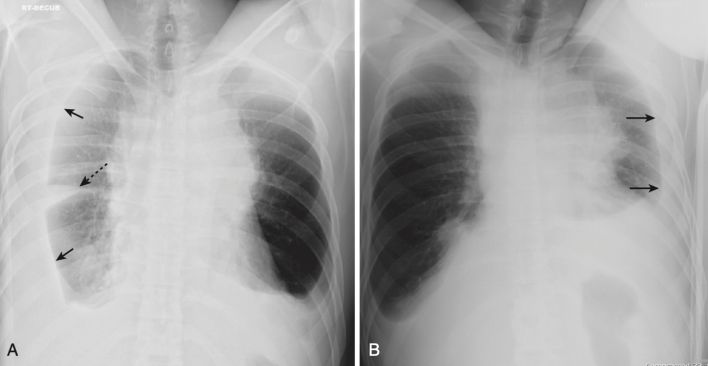

- Hội chứng Dressler (Box 1, Hình 1)

| Box 1 HỘI CHỨNG DRESSLER |

|---|

| Còn được gọi là hội chứng sau phẫu thuật cắt màng tim / sau nhồi máu cơ tim. Thường xảy ra từ 2 đến 3 tuần sau nhồi máu cơ tim xuyên thành, gây tràn dịch màng phổi trái, tràn dịch màng ngoài tim và bệnh vùng khoảng chứa khí từng đám ở đáy phổi trái. Kèm với đau ngực và sốt, nó thường đáp ứng với aspirin hoặc steroid liều cao. |